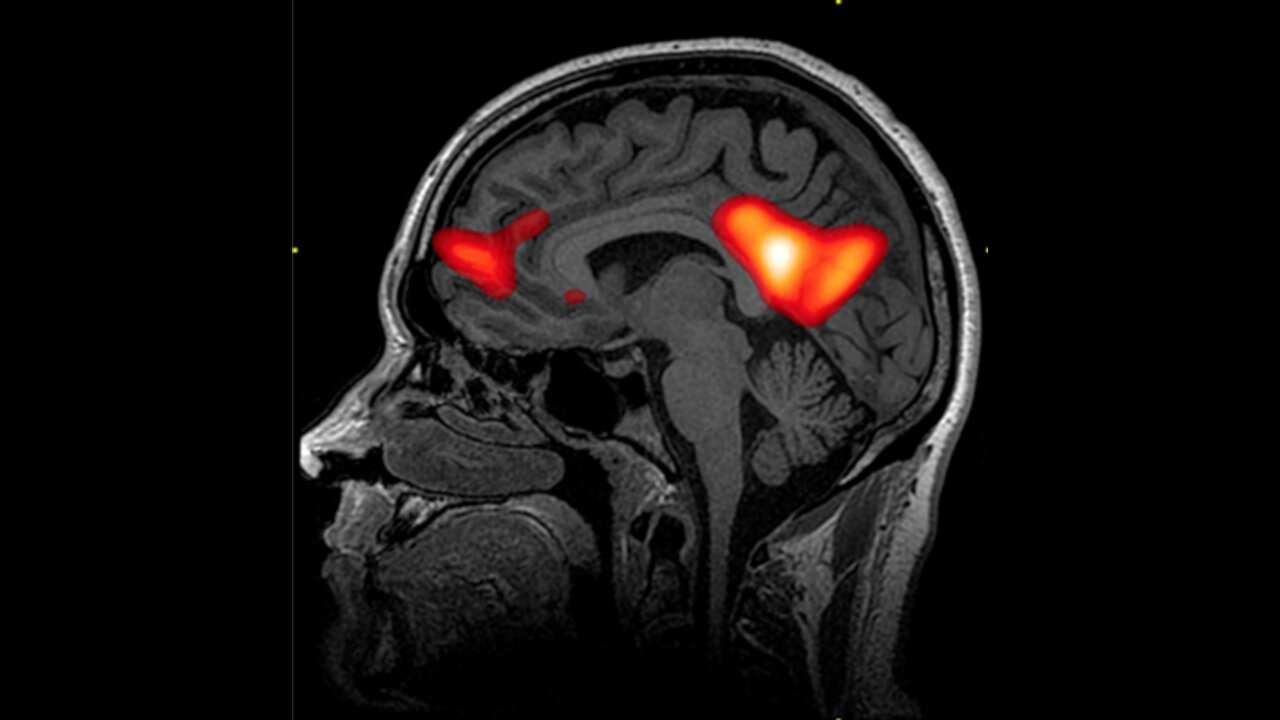

This Is Your Brain In Love